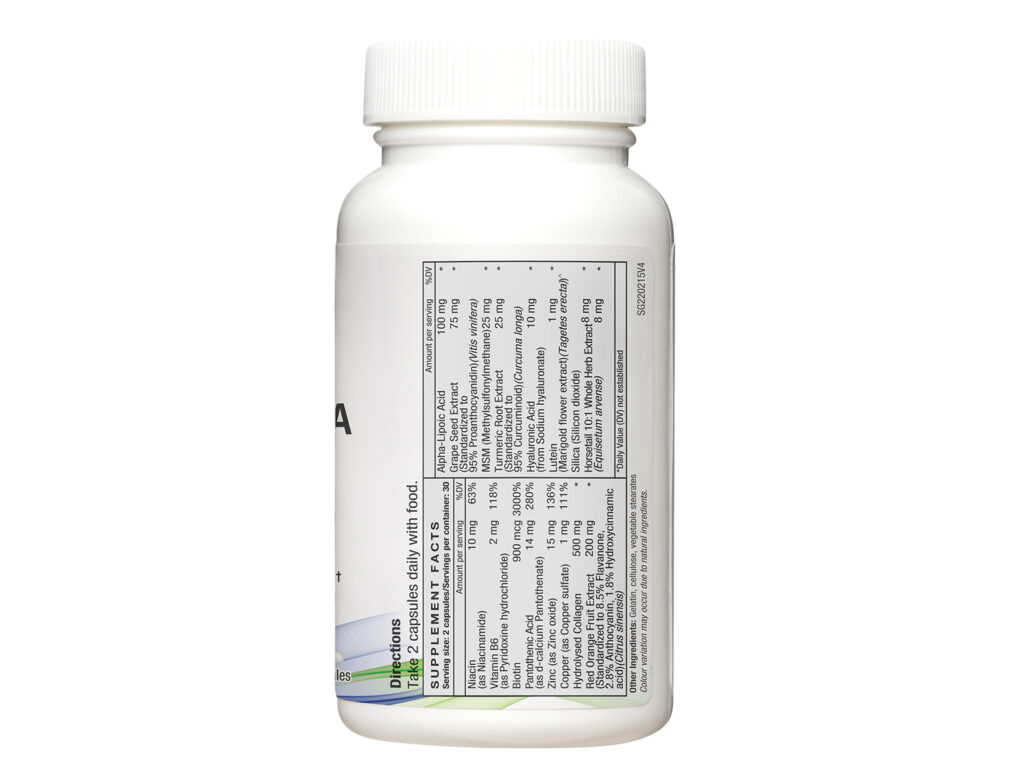

| Ingredients | Amount Per Serving |

| Fermented Soybean Extract

(Nattokinase Activity 20,000FU/g) |

100 mg |

| Hawthorn Extract (Crataegus cuneata, Crataegus pinnatifida) | 100 mg |

| Lecithin | 30 mg |

| Net Weight/pcs | 0.07 kg |

|---|---|

| Direction of Use | As a dietary supplement, take 1 vegicap daily. For individuals aged 18 and above. |

| Serving Size | 1 Vegicap |

| Servings per Container | 30 |

| Country of Origin | Manufactured in Japan |